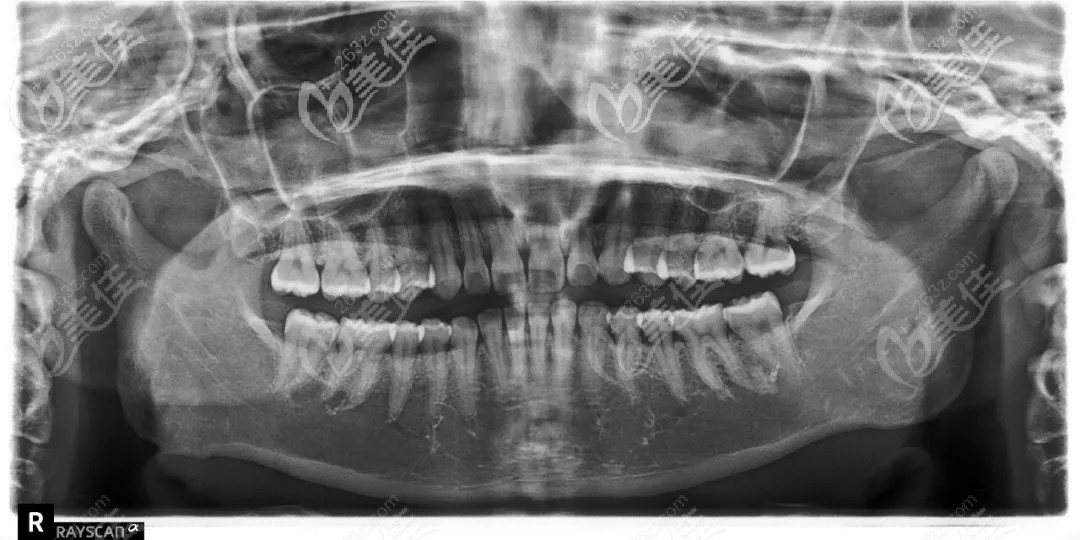

在朋友的推薦下來到了南寧柏樂口腔,拍片經(jīng)過醫(yī)生面診后,才解開了自己心中的謎,原來我的嘴突和下巴短是由于深覆合深覆蓋導(dǎo)致的(這個專 業(yè)術(shù)語之前都沒有聽說過),也就是大家俗稱的天包地,咬牙時上前牙切緣蓋過下前牙牙冠長度 1/3 以上或下前牙咬合于上前牙舌側(cè) 1/3 以上。

下定決心之后,醫(yī)生開始和我聊設(shè)計方案,采用的是推磨牙向后的方式來調(diào)整磨牙關(guān)系,協(xié)調(diào)前牙覆合覆蓋;24歲的我正是在乎美觀性的時候,而且生活和工作中要經(jīng)常和別人交流,所以我選擇了摘戴方便,透明隱適美矯正器(丟三落四的人不建議選擇)。

總的來說,就是看到自己現(xiàn)在一點(diǎn)點(diǎn)的變化,感覺挺值得的,隱適美推磨牙向后一點(diǎn)也不后悔;所以,過來人告訴你,矯正一定要趁早,而且拍片真的很重要,不拍僅僅憑肉眼看,都不知道自己的問題。